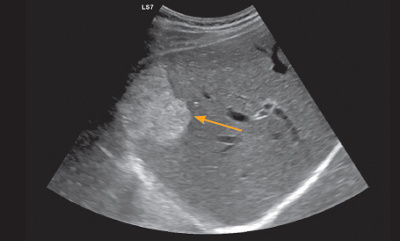

Ein Hämangiom aber bei vielen Herden muß man in erster Linie an Metastasen denken die alle Erscheinungsformen annehmen können insbesondere bei der von Ihnen beschriebenen Krankengeschichte. Ich kenn mich da nun überhaupt nicht aus und sie auch nicht. Außerdem der Preis ist im Bezug auf die angeboteten Qualität überaus angemessen.

September eine PET-Untersuchung machen. Helle Flecken auf der Leber bei Ultraschall Helle Flecken bedeuten im Ultraschall hyperreflexiv. Es entsteht aus dem roten Farbstoff der Blutzellen und wird normalerweise mit Hilfe der Leber ausgeschieden.

Nun meinte der Arzt aber man habe weiße Flecken auf der Leber ausgemacht und er müsse am 30. Zuständige Aufsichtsbehörde in datenschutzrechtlichen Fragen ist die Landesdatenschutzbeauftragte des Landes NRW Kavalleriestraße 2-4 40213 Düsseldorf. Es gibt auch gutartige Veränderungen die hyperreflexiv sind zB. Die Haut verrät nicht nur dass die Leber geschädigt ist sondern auch wie groß das Problem ist. Wohingegen Lebermetastasen eher weniger durchblutet sind. Im Landkreis Wolfenbüttel wird der Ultraschall mit Kontrastmittel nur im Städtischen Klinikum Wolfenbüttel in der Klinik für Innere Medizin und Gastroenterologie angeboten auch ambulant für alle Patienten mit entsprechender Überweisung. Ein Leberzellkarzinom oder ein Blutschwamm wären aktiv durchblutet. Nun meinte der Arzt aber man habe weiße Flecken auf der Leber ausgemacht und er müsse am 30. Helle Flecken auf der Leber bei Ultraschall Helle Flecken bedeuten im Ultraschall hyperreflexiv.